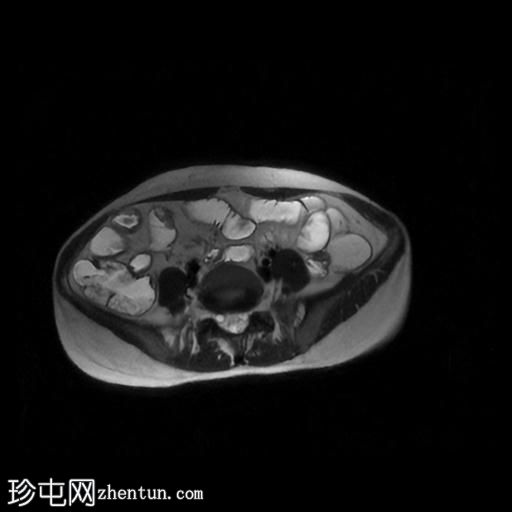

冠状位T2加权像

脂肪抑制

轴位

T2加权像

轴位T1加权像

增强脂肪抑制

冠状位T1加权像

回肠末端及盆腔回肠肠袢可见长段肠壁增厚及强化,肠周血管丰富,呈“梳状征”,并可见明显的纤维脂肪浸润。

未见瘘管、积液、腹水或梗阻。

磁共振肠道造影(MRE)结果支持克罗恩病的诊断,显示远端及末端回肠以活动

性病

变为主,并可见明显的肠周血管。